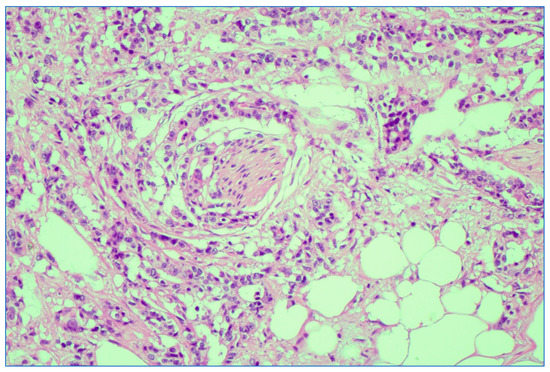

We analyzed the correlation between adjuvant chemotherapy treatment and histopathology bulletin results by using the Pearson correlation coefficient and applying the two-tailed significance t-test. The correlation between adjuvant chemotherapy and a pathological T staging greater than 2 (y)pT > 2 (Figure 6) and between adjuvant chemotherapy and a positive pathological N staging (y)pN > 0 was tested. Other risk factors from the histopathology report that were taken into account were the presence of lymphovascular invasion LVI+ (Figure 7), the presence of perineural invasion PNI+ (Figure 8), positive resection margins Postop+, or a histopathological grade greater than 1 Grade > 1.

Figure 7. Depiction of extramural lymphovascular invasion; carcinomatous emboli of rectal adenocarcinoma. HE stain × 20 magnification.